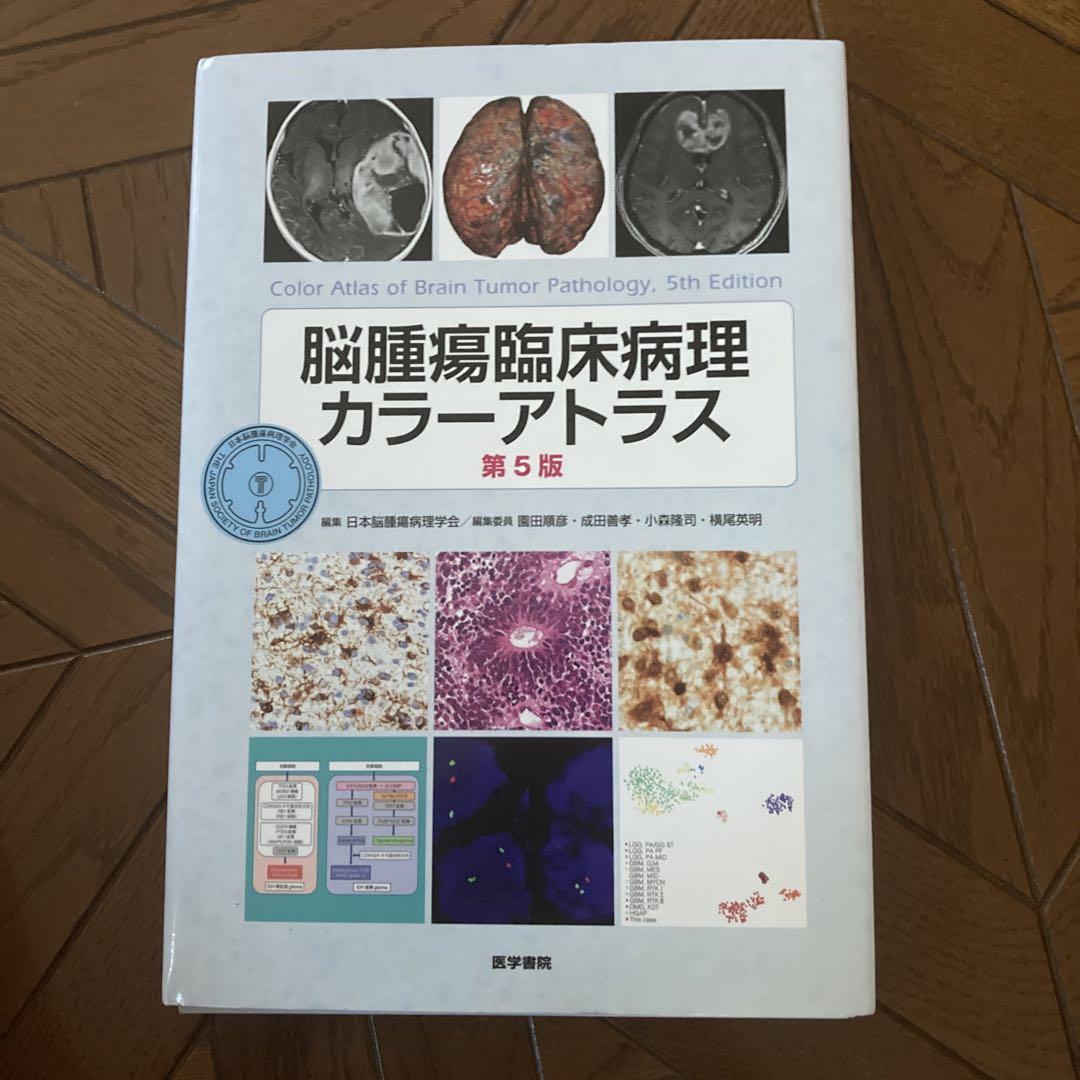

【裁断済み⠀】脳腫瘍臨床病理カラーアトラス 第5版

¥ 8500